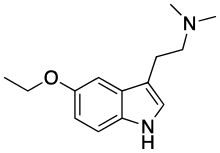

| 5-Ethoxy-DMT | artificial | 5-OCH2CH3 | CH3 | CH3 | 5-ethoxy-N,N-dimethyltryptamine | 855245-09-9 |